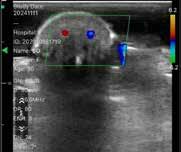

58 Case Study: Using Ultrasound for NSR Complications

Professor Alwyn D’Souza and Dr Farid Hosseini discuss ultrasound in the nose